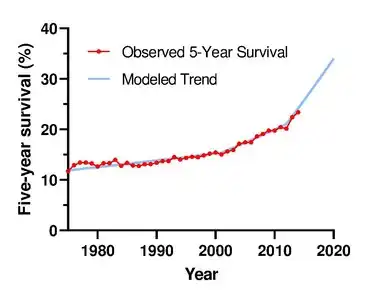

Treatment for early stage lung cancer includes surgery to remove the tumor, sometimes followed by radiation therapy and chemotherapy to kill any remaining cancer cells. Later stage cancer is treated with radiation therapy and chemotherapy alongside drug treatments that target specific cancer subtypes. Even with treatment, only around 20% of people survive five years on from their diagnosis.[5] Survival rates are higher in those diagnosed at an earlier stage, diagnosed at a younger age, and in women compared to men.

Around 19% of people diagnosed with lung cancer survive five years from diagnosis, though prognosis varies based on the stage of the disease at diagnosis and the type of lung cancer.[5] Prognosis is better for people with lung cancer diagnosed at an earlier stage; those diagnosed at the earliest TNM stage, IA1 (small tumor, no spread), have a two-year survival of 97% and five-year survival of 92%.[58] Those diagnosed at the most-advanced stage, IVB, have a two-year survival of 10% and a five-year survival of 0%.[58] Five-year survival is higher in women (22%) than men (16%).[5] Women tend to be diagnosed with less-advanced disease, and have better outcomes than men diagnosed at the same stage.[59] Average five-year survival also varies across the world, with particularly high five-year survival in Japan (33%), and five-year survival above 20% in 12 other countries: Mauritius, Canada, the US, China, South Korea, Taiwan, Israel, Latvia, Iceland, Sweden, Austria, and Switzerland.[60]

- ^ a b c Goldstraw et al. 2016, "Figure 2".